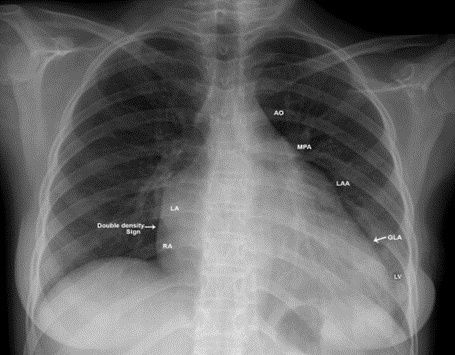

Figure 9. X-ray chest PA (postero-anterior) view showing the dilated LA (left atrium) towards left chest wall in an isolated severe rheumatic mitral regurgitation in a 18-year old girl. The left heart border is ‘4-bump’ as aortic knuckle (AO), MPA (main pulmonary artery), LAA (dilated convex left atrial appendage-third mogul sign) and LV (left ventricle). Right arrow- showing the ‘Double density sign’ of LA enlargement in the right heart border. Left arrow- showing the GLA (giant left atrium) reaching the left chest wall.

Figure 11. Parasternal long axis view showing the aneurysmal left atrium in a 18-year old girl due to pure rheumatic mitral regurgitation

In mitral regurgitation, the left atrial size is proportionately related to compliance and the dilated left atrium compensates for increased stress by an initial increase in compliance. This reservoir effect of a large left atrium is beneficial to protect the lungs from pulmonary hypertension and edema [28],[29]. Increased left atrial and pulmonary pressures, in case of very large left atrium ( > 60 mm) provide the substrate as a structural precursor of atrial fibrillation [30],[31] which contributes further atrial dilation in mitral valve disease [32]. The dilated atrium requires more energy to pump blood and lose its elastic properties due to myocarditis, succumbs to deformational change, limiting Laplace’s law application in chronic mitral regurgitation and becomes larger with an increase in LA volume. For an LA diameter of 6 cm, the estimated volume of atrium exceeds 300 ml [33]. The increased LA volume may complicate thrombus formation due to potential stasis with thromboembolic events. The enlarged left atrium may compress the bronchial tree (widening of carinal angle (splaying of carina) > 120 ₀ as shown in Figure 3, stenosis of left main bronchus), left laryngeal nerve (hoarseness due to left vocal cord paralysis- Ortner’s syndrome [34],[35]), inferior and middle lobes of right lung (atelectasis, infection) [36], postero-basal part of left ventricle as in Figure 17 (hemodynamic instability) and esophagus (dysphagia). Isolated LV compression by Giant LA is defined as Type 1 [37], both LV and bronchopulmonary compression is defined as Type II [38] Giant left atrium. Nigri reported a rare complication of giant left atrium, pushing the heart to the right side of the chest and mimicking as dextrocardia [39],[40]. The left atrium extends more to the left side forming the left atrial appendage which becomes convex in the left heart border (third Mogul sign) just below the pulmonary trunk when it is dilated (normally it should be flat or slightly concave) and makes a “4-bump” left heart border as in Figure 3 and 9 that includes the aortic knob, main pulmonary artery, left atrial appendage, and the left border of left ventricle. In mitral stenosis, the body of left atrium is larger than normal and it never produces a giant left atrium, but giant left atrium with rheumatic mitral stenosis was reported [41] and it may be associated with massive thrombus formation as shown in Figures 21 to 24.